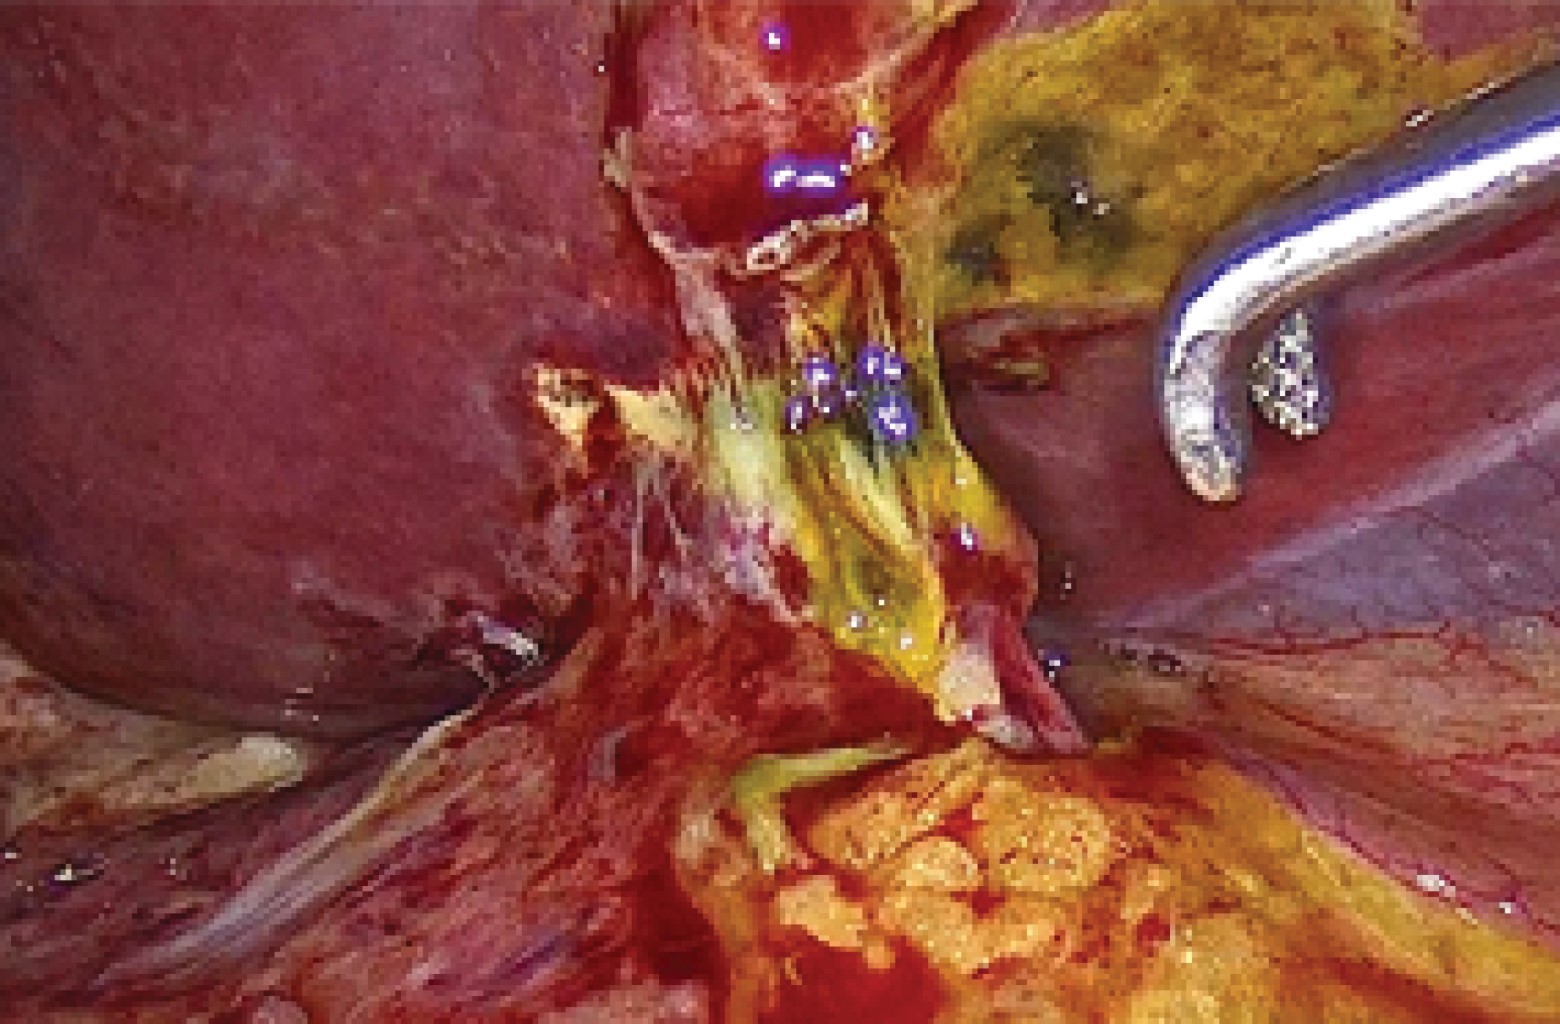

Introduction: laparoscopic cholecystectomy is the gold standard for gallstone disease, however, it is not free of complications, such as hemorrhage, seroma, biloma, biliary leakage, surgical wound infection and bile duct injury, being the presence of aberrant ducts one of the main risk factors. The anatomical variations of the biliary tract are due to alterations in the embryological development, it is important that the surgeon knows how to recognize them, since during cholecystectomy there is a risk of ligation, section, biliary leak or stenosis of an accessory or aberrant duct. Biliary leaks have increased since the standardization of laparoscopic cholecystectomy, with a frequency of approximately 0.3-0.5%. Endoscopic retrograde cholangiopancreatography (ERCP) is the ideal study, since it confirms the diagnosis by identifying the site of biliary leakage and during the same procedure sphincterotomy and stent placement can be performed, allowing closure of the defect, with a success rate of more than 90%. Clinical cases: we present two cases of biliary leakage after laparoscopic cholecystectomy secondary to the presence of anatomical variations of the extrahepatic biliary tract, both manifested by abdominal pain requiring hospitalization. In the first case the biliary leak was evidenced during ERCP and was resolved with the placement of a stent. The other case, having a negative ERCP and persistence of abdominal pain, underwent diagnostic laparoscopy, finding a biliary leak from an accessory duct, for which a new transoperative ERCP was performed for stent placement. Conclusion: these two cases are very interesting because despite being the same type of biliary leak, they presented differently, one at 72 hours postoperatively and the other at eight days. Likewise, one of them was resolved by ERCP and the other had a negative ERCP before the definitive diagnosis could be made. Therefore, a high index of suspicion of biliary leakage through an accessory or aberrant duct should be taken into account when faced with abdominal pain after laparoscopic cholecystectomy.

Figure 2